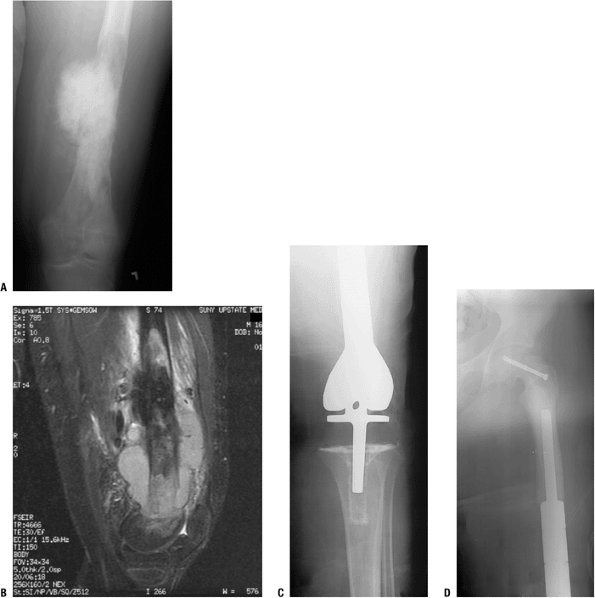

radiographs (A,B) and an axial T1-weighted magnetic resonance image (C). (D,E) Postoperative AP and lateral radiographs.P.70 Figure 4.3-11 (A,B) Figure 4.3-11 (A,B)

In this skeletally immature patient with a proximal tibial Ewing

sarcoma, the tibia was reconstructed using an expandable prosthesis,

maintaining the distal femoral physis. (C)

This specific expandable prosthesis has a deformable resin, which, when

placed in a magnetic coil, allows expansion of the encased preloaded